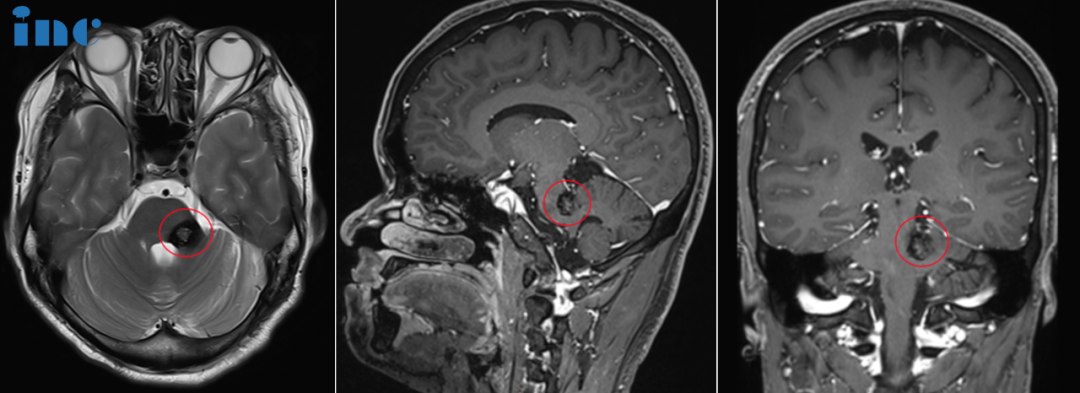

脑干海绵状血管瘤手术风险大,可以选择放疗或者药物治疗吗?46岁女士突然感到左侧面部麻木。检查显示大出血性轴内桥脑海绵状血管瘤(A和B)。脑桥的背侧结构受到严重压缩(红色箭头),表明仅在病变和菱形窝表面之间有薄薄的实质层。